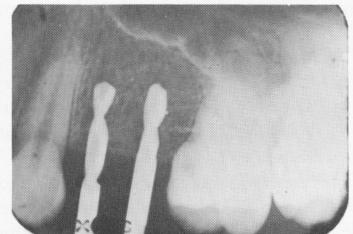

Fig. 8-13. Two self-tapping vent-plants in their proper positions.

2 Self-tapping upper endosseous vent-plants implants in proper position